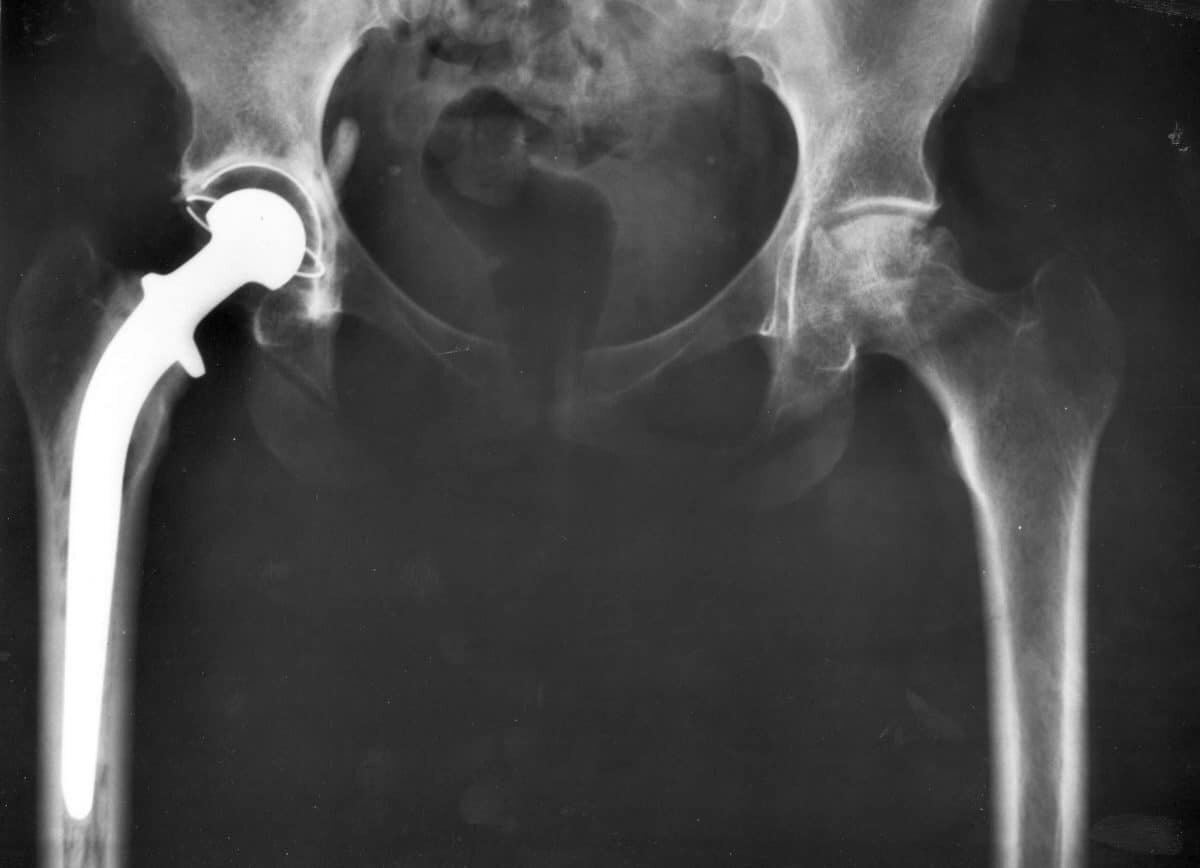

Рентген после эндопротезирования тазобедренного сустава / © NIADDK, 9AO4 (Connie Raab-contact), National Institutes of Health / Wikipedia

Современная медицина достигла значительных результатов в области замены поврежденных суставов. Подобные операции сегодня стали высокоточными процедурами, позволяющими пациентам не просто избавиться от хронической боли, а вернуться к полноценной активной жизни. По последним данным, примерно 200 тысяч человек в России ежегодно нуждаются в полной замене тазобедренного сустава. Такая потребность делает важным не только доступность самой операции, но и создание имплантатов, которые служили бы десятилетиями без риска отторжения и повторных операций.